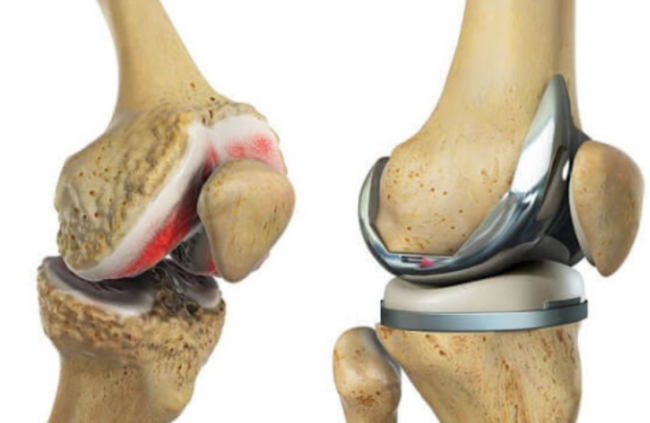

1. 무릎 인공관절 수술이란?

무릎 인공관절 수술은 퇴행성 관절염이나 관절 손상으로 인해 정상적인 생활이 어려운 분들을 위해 손상된 관절을 금속 또는 플라스틱 인공관절로 치환하는 수술입니다.

- 일반적으로 치환술이라고도 하며, 전치환(전체 교체)과 부분 치환술로 나뉩니다.

6. 무릎 인공관절 수술 후 부작용 – 염증 주의

- 초기 통증 외에도 드물게 세균 감염으로 인한 염증이 생길 수 있음